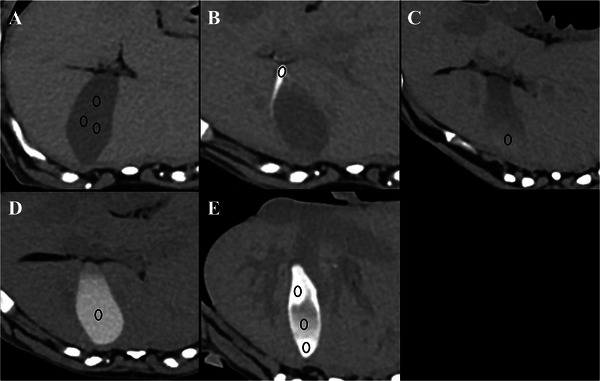

Vicarious excretion is a nonrenal pathway of excretion for intravenously injected iodinated contrast media, with a limited understanding of its influencing factors and imaging features. In this prospective pilot study, gallbladder opacification (GBO) and small intestinal luminal opacification (SILO) were assessed to identify vicarious excretion patterns following intravenous contrast media administration for CT in clinically healthy dogs. Eight beagles were studied using a crossover method, divided into fed and fasted groups. The fed group was fed at 5 and 13 h after the first CT scan, while the fasted group was fed only at 13 h. Noncontrast and postcontrast CT scans were performed at 90 s, 10 min, 1 h, 4 h, 12 h, and 24 h after iohexol injection. The GBO was subjectively scored from grade 0 to 5 based on the attenuation value and area of opacification. The SILO was evaluated subjectively based on contrast intensity (weak or marked) and distribution. The GBO was observed from 1 h after contrast injection. Significant differences were noted in median GBO scores within the groups at 4, 12, and 24 h on Friedman's test followed by the post hoc Wilcoxon signed-rank test. The scores were significantly higher in the fasted group at 12 h on the Wilcoxon signed-rank test. The SILO occurred 10 min after contrast administration, with various distributions. In conclusion, GBO and SILO can be observed during delayed CT phases, and fasting increases the intensity and duration of GBO in clinically healthy dogs. These findings should not be interpreted as pathological changes.

静脉注射碘造影剂的替代排泄是一种非肾性排泄途径,对其影响因素和影像学特征的了解有限。在这项前瞻性先导研究中,对临床健康犬的胆囊混浊(GBO)和小肠腔混浊(SILO)进行评估,以确定静脉注射造影剂后的替代排泄模式。8只小猎犬采用交叉实验方法进行研究,分为进食组和禁食组。饲喂组在CT首次扫描后5、13 h饲喂,禁食组仅在13 h饲喂。注射碘己醇后90 s、10 min、1 h、4 h、12 h、24 h分别进行非对比和对比后CT扫描。根据衰减值和混浊面积对GBO进行0 ~ 5级主观评分。根据对比强度(弱或明显)和分布对SILO进行主观评价。注射造影剂1 h后观察GBO。在弗里德曼检验和事后Wilcoxon符号秩检验中,4、12和24小时组内GBO得分中位数有显著差异。在12小时的Wilcoxon sign -rank检验中,禁食组的得分明显更高。SILO发生于给药后10分钟,且分布不同。综上所述,在CT延迟期可以观察到GBO和SILO,在临床健康犬中,禁食可以增加GBO的强度和持续时间。这些发现不应被解释为病理改变。